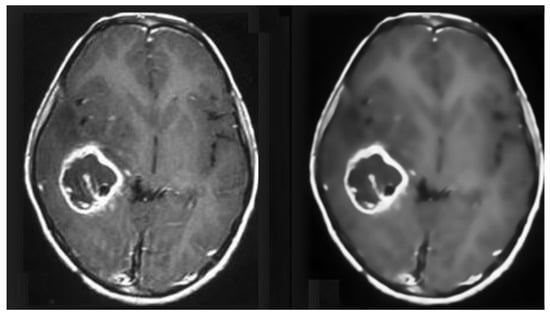

3.3.2. Pre-Processing of MRI Data

MRI images suffer from Rician noise. The presence of noise can affect the accuracy of the classification model. Therefore, this noise needs to be removed before any classification can be performed in the pre-processing stage. For this purpose, an FSNLM filter was used. This technique uses fuzzy logic to find segments in the image that are homogeneous to the noisy pixel. Once these segments have been identified, they can be used to find the noise-less pixel. The FSNLM filter’s advantage over other denoising techniques is its low computational cost and its ability to retain the level of details in the MRIs. The FSNLM has been reported with a mean PSNR of 19.7 for T1 weighted images and 17.5 for T2 weighted images [22]. Figure 8 shows the actual noisy and denoised MRI.

Figure 8. Pre-processed MRI data (Before and After Denoising).